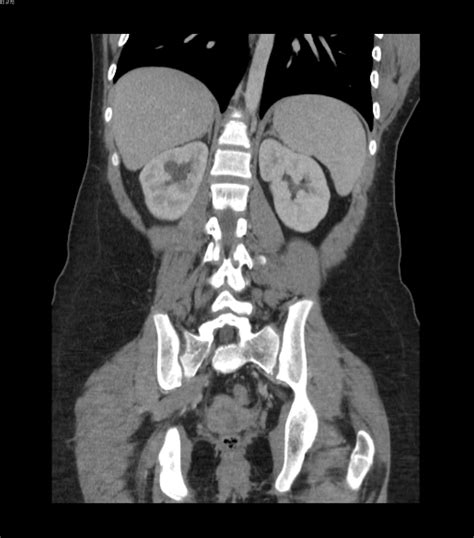

Understanding the intricacies of a CT Scan IVP (Computed Tomography Intravenous Pyelogram) is crucial for both medical professionals and patients. This diagnostic procedure combines the power of computed tomography (CT) with intravenous contrast to provide detailed images of the urinary system. By injecting a contrast dye into the bloodstream, the CT scan can highlight the kidneys, ureters, and bladder, making it easier to detect abnormalities such as stones, tumors, or blockages.

A CT Scan IVP is a specialized imaging technique that uses X-rays and computer technology to create detailed cross-sectional images of the body. The intravenous contrast dye enhances the visibility of the urinary system, allowing radiologists to identify issues that might not be apparent with standard X-rays or other imaging methods. This procedure is particularly useful for diagnosing conditions affecting the kidneys, ureters, and bladder.

After the CT Scan IVP, the radiologist will review the images to identify any abnormalities in the urinary system. The results are typically available within a few hours to a few days, depending on the facility. The radiologist will provide a report to the referring physician, who will then discuss the findings with the patient.

Some common findings from a CT Scan IVP include:

• Kidney stones or other obstructions in the urinary tract.

• Tumors or cysts in the kidneys, ureters, or bladder.

• Infections or inflammation in the urinary system.

• Structural abnormalities, such as congenital defects or injuries.